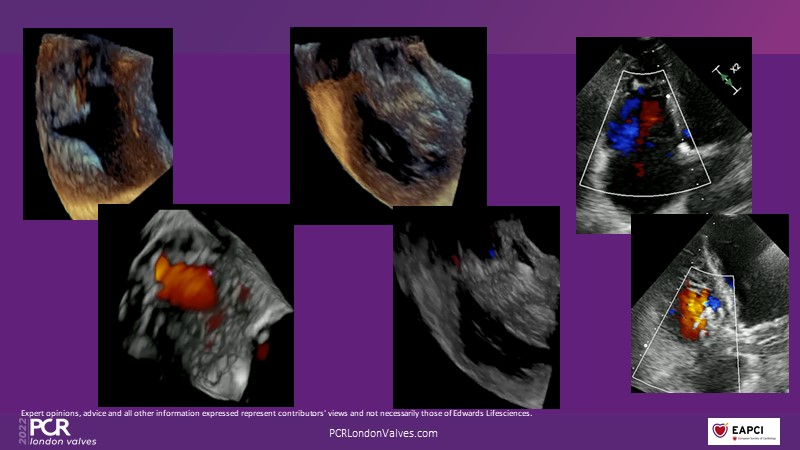

This innovative session takes you through the patient selection and anatomical characteristics when selecting amongst the different transcatheter options to treat tricuspid regurgitation, followed by a recorded demonstration using the PASCAL Precision repair system.

- To discuss the anatomical considerations that define suitable candidates for the different portfolio of options to treat tricuspid regurgitation

- To review different transcatheter options to treat tricuspid regurgitation and their key differentiators